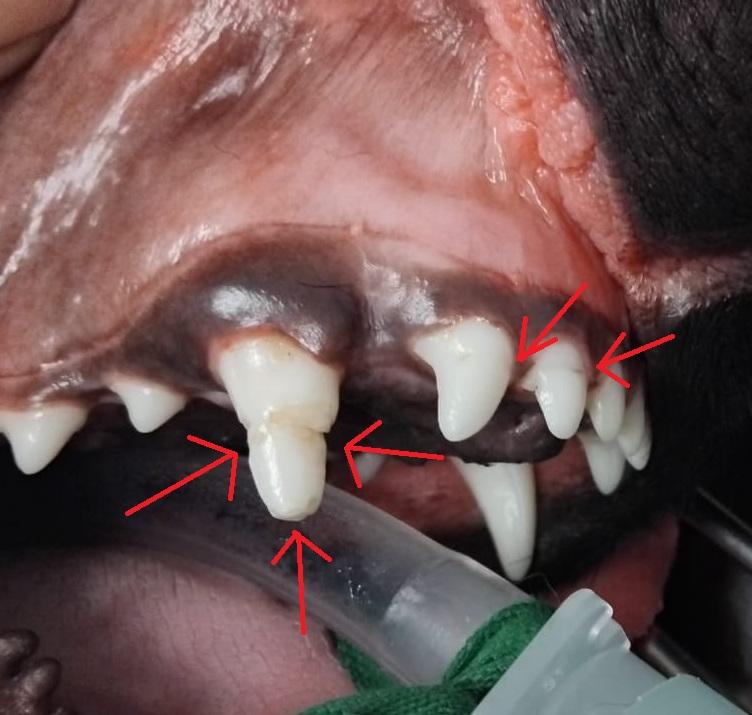

C'est le cas de Alphonse, qui nous a été présenté en vue de sa castration à l'âge de 9 mois, et dont l'anomalie dentaire est une découverte fortuite de la consultation.

L'origine de l'anomalie n'est pas connue. Les deux incisives adjacentes au croc étant également atteintes, il est probable qu'il s'agisse d'une malformation de l'émail, probalement traumatique, quand ces dents étaient au stade de bourgeon dentaire.